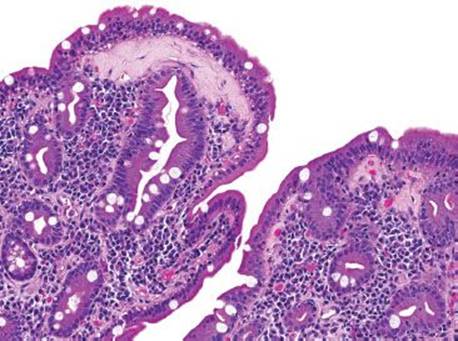

Figure 3.316 Isosporiasis. This intermediate power view shows how easy it is to miss Isospora. At low power, only gastric foveolar metaplasia and perhaps a slight increase in lamina propria eosinophils is seen. Other fields of this same case were essentially normal, emphasizing that every biopsy needs a few high power fields of attention for such extremely subtle diagnoses.

Isosporiasis is among the more common protozoan causes of severe diarrhea in AIDS patients (Figs. 3.316–3.318).190 The Isospora belli organisms are spread via contaminated water or fecal–oral contamination. They localize to the small bowel surface and are exceedingly easy to miss owing to sometimes unremarkable background mucosa and sparsely distributed organisms (Figs. 3.316–3.321). Diagnostic confirmation is facilitated through identification of the oocysts in stool samples or duodenal aspirates.191 Standard therapy consists of trimethoprim–sulfamethoxazole, which is often long term in severely immunocompromised patients.